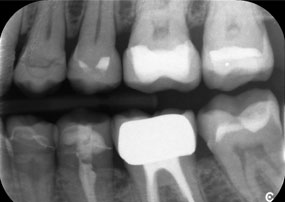

Рентгенова снимка, показваща зъби и циркониева корона.

Фигура 2: Подмяна на увредена циркониева корона: Прецизно отстраняване и подмяна на увредена циркониева корона на зъб 6 с минимална загуба на материал.